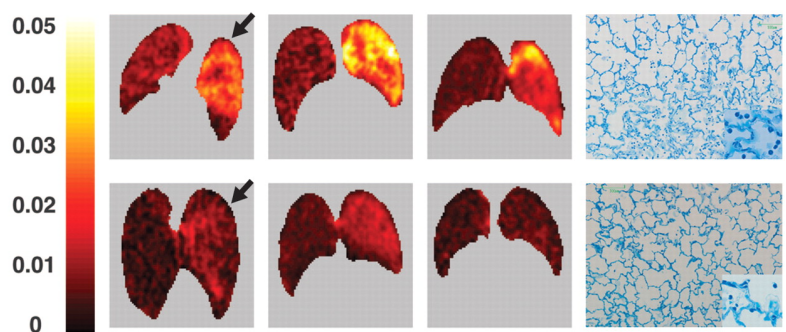

肺通气的超声征象分为四组:①正常模式(N),表现为肺滑动征伴A线或孤立的B线(<3),记0分;②肺通气中度丧失,出现多条B线(>3),记1分;③严重的肺通气损失,显示为融合B线,记2分;④肺组织实变征象记3分。在分析过程中,每一个特定的区域最差的超声波征象为计分标准,并将所有点的得分相加。结果显示,肺部超声评分(LUS)与多个ARDS预后指标[血管外肺水指数(EVLWI),肺损伤评分(lung injury score,LIS),呼吸系统顺应性(Crs),氧合指数]密切相关,能够准确评估ARDS治疗的疗效,如PEEP的设定、肺复张的疗效,并能够预测ARDS患者死亡风险。与其他检查相比,肺部超声是一种无创、经济、可重复、简单的床旁检查方法,但肺气肿、肥胖、导管敷料等都影响超声的评定,测量参数有一定的主观性。弥漫性肺泡损伤(DAD)是ARDS的病理标志。一项研究分析了是否可以使用高分辨率CT(HRCT)评分来预测与DAD相关的60 d死亡率,研究共纳入34例在ARDS诊断后7 d内接受HRCT的DAD患者,并被分为60 d存活组和未存活组,每组17例患者。采用Ichikado等提出的HRCT评估急性间质性肺炎评分系统评估ARDS,HRCT表现根据分级系统按1~6分进行评分,1分为正常衰减,2分为磨玻璃影,3分为实变,4分为磨玻璃影伴牵引性支气管扩张或细支气管扩张,5分为实变伴牵引性支气管扩张或细支气管扩张,6分为蜂窝状。单因素和多因素二元回归分析以及ROC曲线显示,牵引性支气管扩张或细支气管扩张的总面积百分比是60 d死亡率的独立预测因子,具有良好的预测性能。存活患者的HRCT表现为广泛的磨玻璃影和实变,支气管壁光滑(图4B)。未存活患者的HRCT表现为双侧磨玻璃影、网状和明显的牵引性支气管扩张(图4D红色箭头)。图源:J Clin Med, 2022, 11(9):2458.肺部炎症是ARDS的关键特征之一。氟代脱氧葡萄糖(FDG)是一种具有生化活性的葡萄糖抗代谢产物,FDG被组织细胞吸收后可在PET-CT扫描显像。中性粒细胞活化在代谢上的特征是每个细胞的葡萄糖利用率增加,从而增加FDG摄取。在急性肺损伤(ALI)期间,FDG PET可用于监测肺中性粒细胞活化情况。同时,在ALI状态下,巨噬细胞对FDG信号的变化较小,淋巴细胞在体外激活后FDG摄取增加。内皮细胞活化后具有高度代谢活性,摄取FDG增强,肺泡上皮细胞受损后也可以促进FDG的摄取。因此,FDG PET可能是一种有价值的非侵入性方法,可用于全面了解ALI/ARDS的发病机制,早期预测ARDS的发生和评估预后。研究发现,单侧吸入烟雾导致急性损伤的单侧绵羊肺中区域FDG摄取显著增加(图5,图6)。在该模型中,区域FDG标记葡萄糖摄取可以预测区域气体交换损伤,表明存在功能-炎症关系。研究结果还表明,损伤前的通气-灌注异质性程度与损伤后FDG摄取的程度之间存在直接关联。

图5  单纯吸入烟雾的绵羊肺

图源:AJR Am J Roentgenol, 2010, 195(2):292-300.图6  单纯吸入烟雾以及吸入烟雾和呼吸机肺损伤双重打击的绵羊肺图源:AJR Am J Roentgenol, 2010, 195(2):292-300.Musch等发现在机械通气后90 min,在呼吸机诱发的肺损伤绵羊模型中可以检测到仅由机械力引起的区域FDG摄取增加(图7)。图7  三只羊暴露于单侧呼吸机引起的肺损伤,早期出现FDG浓聚图源:AJR Am J Roentgenol, 2010, 195(2):292-300.Rodrigues等针对FDG PET的预测价值对8例肺挫伤患者进行了研究,其中没有一例患者最初符合ARDS的标准。入院后24~72 h,在FDG PET中,后来发生ARDS的4例患者中有3例在整个肺部有弥漫性FDG摄取,但后来未发生ARDS的4例患者仅在CT图像上局灶性肺混浊区域有显著的FDG摄取(图8)。后来发生ARDS的患者正常通气肺的FDG摄取值高于未发生ARDS的患者,这表明FDG PET在ALI早期阶段提供了很有价值的预测信息。图8  因胸部创伤和肺挫伤入院的患者,高浓聚者后来发生ARDS图源:AJR Am J Roentgenol, 2010, 195(2):292-300.6. 运用生物信息学和转录组学技术筛选ARDS预后标志物在ARDS肺泡巨噬细胞中发现的转录组学生物标志物可以预测机械通气的危重症患者预后。研究收集了35例受试者的68个BALF样本,这些样本均在ARDS发生48 h内采集,从24526个基因中筛选4个分子——ADORA3,GNB1,NTS,RHO。其中ADORA3(adenosine A3 receptor)主要是调控炎症因子和免疫反应。研究表明,ADORA3及其相关通路变化与28 d死亡率明显相关,ADORA3有可能成为评估ARDS预后的关键基因。有研究纳入2016年1月至2019年6月期间的196例脓毒症患者和入组时196名健康个体的血浆样本。结果发现,与健康人相比,ARDS脓毒症患者和非ARDS脓毒症患者的miRNA-103和miRNA-107均降低,ARDS脓毒症患者的miRNA-103和miRNA-107均低于非ARDS脓毒症患者。miRNA-103和miRNA-107降低预示着脓毒症患者ARDS和28 d死亡风险增加。miRNA-103和miRNA-107是脓毒症ARDS患者28 d死亡率的预测标志物。另外一项研究纳入脓毒症患者150例和健康受试者150例(健康对照)。与健康对照组相比,ARDS脓毒症患者和非ARDS脓毒症患者miRNA-125a和miRNA-125b相对表达增加,而与非ARDS脓毒症患者相比,ARDS脓毒症患者仅miRNA-125b升高,而miRNA-125a没有升高。miRNA-125b在预测ARDS风险方面有较高的价值。